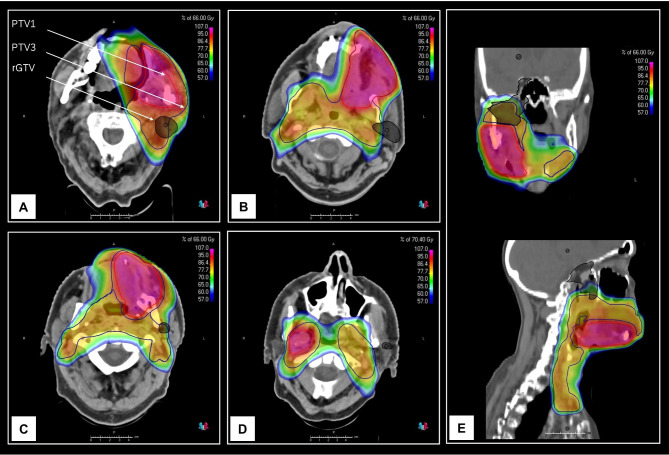

Materials and methods: We retrospectively reviewed 203 HNSCC patients (75% HPV-negative, 25% HPV-positive) treated with curative intent postoperative (chemo)radiotherapy from 2017 to 2021. Recurrence imaging was co-registered with planning CT, and recurrent tumor volumes were dosimetrically compared to the target volume dose and spatially analyzed using a center-of-mass-based approach. We classified five recurrence types: A (central high-dose), B (peripheral high-dose), C (central intermediate- or low-dose), D (peripheral intermediate- or low-dose), and E (extraneous dose).